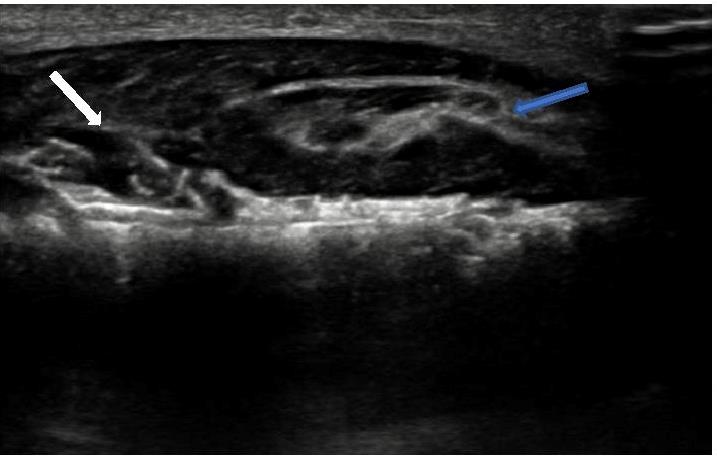

![]() |

Image C : Transverse image proximal ulna : spiculated tumour (white arrow) arising from right ulna with associated soft tissue mass, note preservation of fat plane between tumour & overlying muscle (blue arrow). |